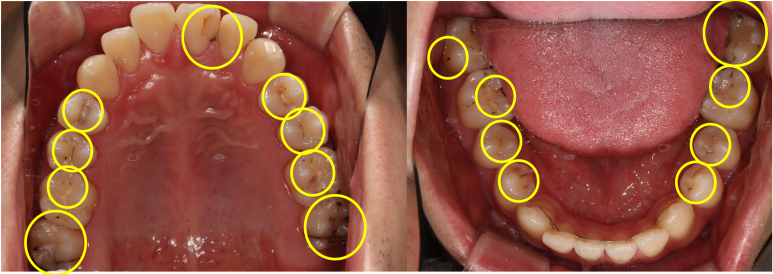

제가 봤을 때 CODE 1 까지는 지켜봐도 될 것 같고, CODE 2부터는 치료를 요한다고 생각이 듭니다.

근데, CODE 4 같은거 보면 좀 덜 썩어보이고.. 그쵸?

솔직히 CODE 2 정도라고 해서 단시간만에 썩는것도 아닙니다.

그래서 같은 치과의사인데 충치 개수는 맨날 다릅니다.

제가 봤을 때 아까 그 분은 충치가 17개라고 해도 뭐.. 틀린말은 아닌 것 같습니다.

근데 저 분류대로 보면,

밑에 표시해둔 파란색 2개 정도는 좀 빨리했으면 좋겠다. 좀 급하다. 라는 생각은 들고,

노란색으로 표시해둔 것들은, 위에서 보시는 CODE 1에 해당되거나, 기존에 치료해둔 것의 변색으로도 보입니다.

그렇지만 기존 재료의 변색은 곧 치아와 재료 사이의 누수(leakage)를 뜻하고, 당연히 교체해주는 것이 원칙입니다. 다시 해야한다는 말이죠..

그럼.. 충치는 2개인가요? 17개인가요?

보여드렸던 환자분의 경우 조금의 생각 차이에 따라 2개가 될수도 17개가 될수도 있는 상황이었어요.